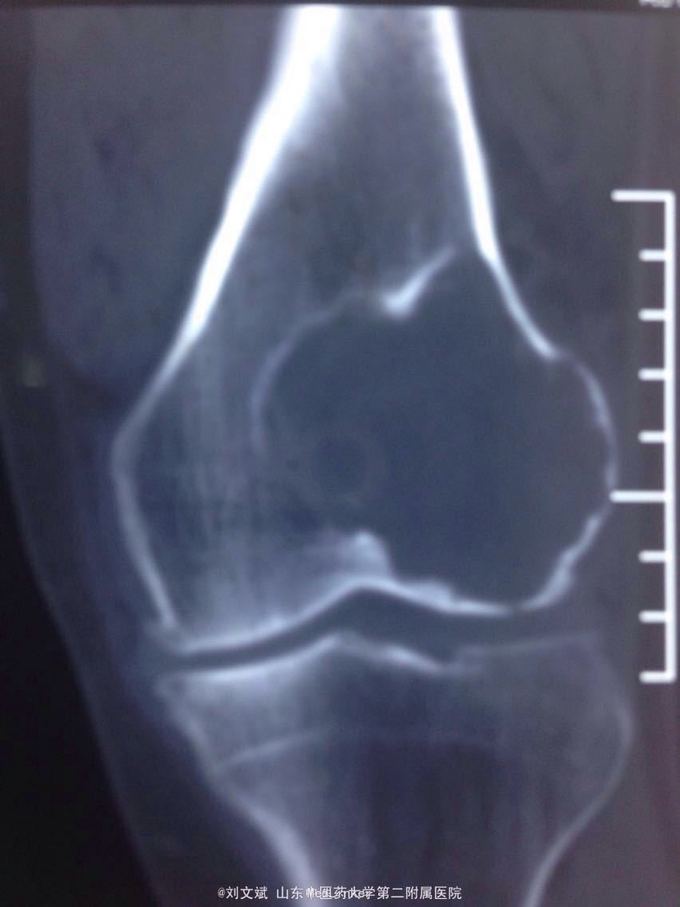

男性51岁,左膝关节疼痛不适10余年。因症状较轻,不影响活动,未曾系统诊治。一月前因扭伤致疼痛加重,拍片检查,见股骨远端骨质异常,进一步行CT示股骨髁占位病变,考虑骨囊肿。既往有高血压,糖尿病病史。近期无低热,体重下降。

左膝关节外观皮色正常,无明显肿胀,屈伸活动未见明显受限,外髁轻度压痛,侧方应力及抽屉试验阴性,半月板回旋挤压试验阴性,浮髌试验阴性。肢端感觉,血运正常。

诊断:左股骨远端占位 因皮质完整,行手术开窗刮除,自体髂骨及同种异体骨混合植骨填充治疗。切取组织送病理检查

刮除占位组织如图所示,送病理检查了,结果还没回来。 没有全身症状,像是原发灶,骨皮质完整,没有明显骨膜反应请专家们看看,什么可能性比较大? 补上病理结果和术后片子